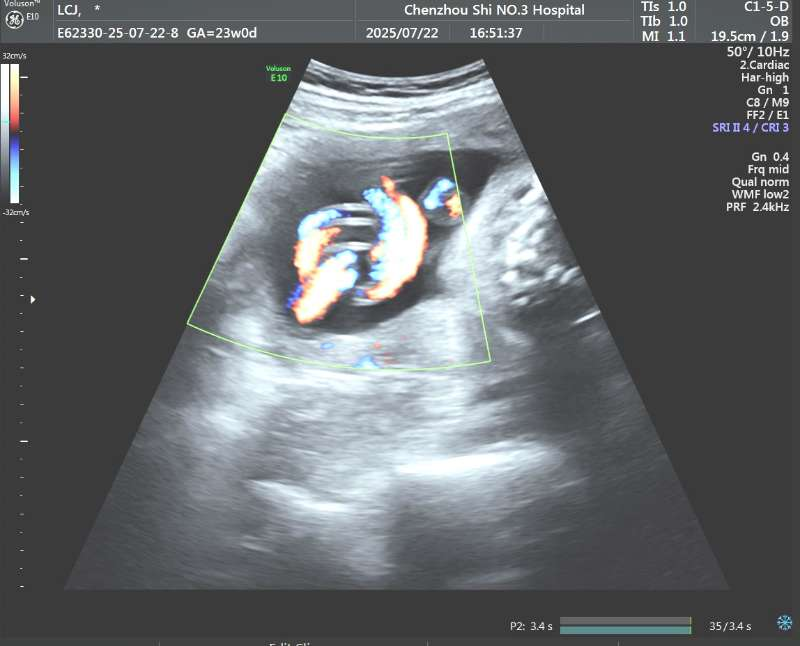

今年7月22日,孕24周的文女士(化名)在我院做四维彩超时,超声中心医生发现胎儿脐带局部堆积、缠绕,凭借专业敏感性和细致操作,医生最终在彩色多普勒图像中识别出一段典型的“环状”交叉结构,而且中心可见连续的血管壁回声。基于这一关键征象,超声团队果断在报告中提示“高度怀疑脐带真结”。